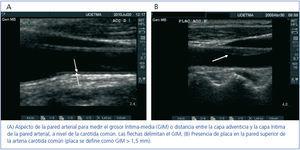

La ecografía de arterias carótidas –medida del GIM y detección de placas de ateroma (figura 1a y b)– es un potente indicador del estado de salud vascular global. La medida del GIM es un marcador implementado y aceptado para la predicción de ECV10.

Figura 1. Ecografías de arterias carótidas